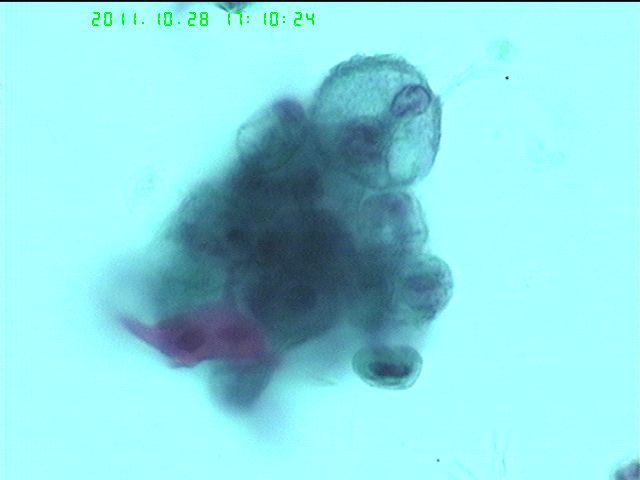

支刷液基,等你诊断

59岁女性第二次支刷液基

打癌没有问题,但是不是每张图都是癌。有些是组织细胞。非小细胞癌。

查见癌细胞  考虑腺癌

腺癌。

考虑鳞癌,有核仁不一定都是腺癌。

倾向腺癌

可能是腺鳞癌,但是在细胞学可以选择保险的报:查见癌细胞,建议活检以明确分类。

活检:鳞癌。谢谢大家参与

图3、5、11其实已经很典型了,粗糙的核,扭曲的核膜,小的核仁,多彩和红染的胞浆,以及细胞的片状、散在结构。

当然事后分析不算数。